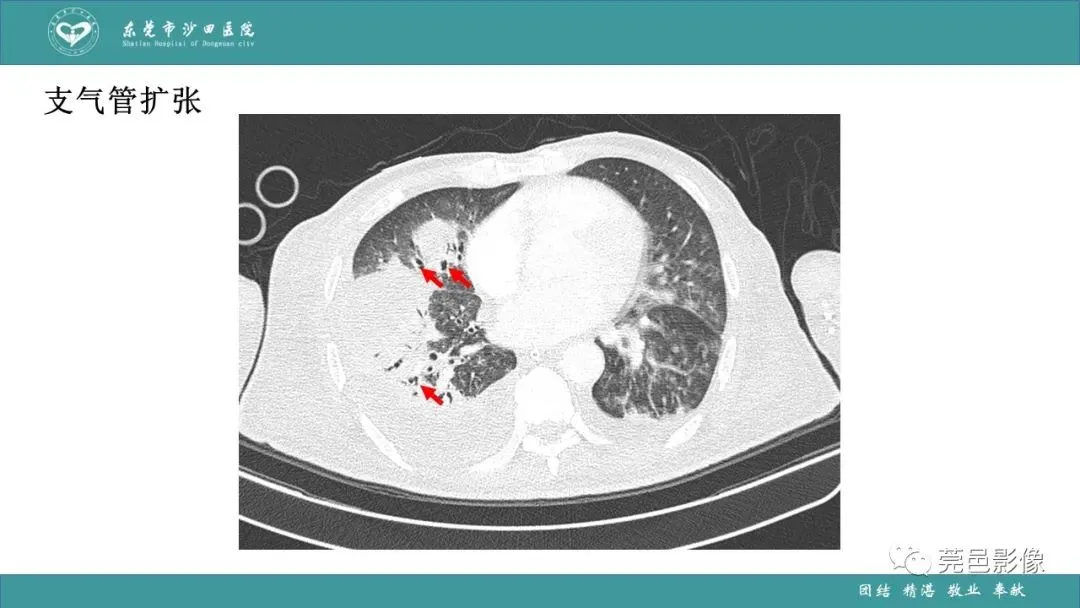

>课件 | 肺炎克雷伯杆菌肺炎影像学诊断与鉴别诊断

课件 | 肺炎克雷伯杆菌肺炎影像学诊断与鉴别诊断